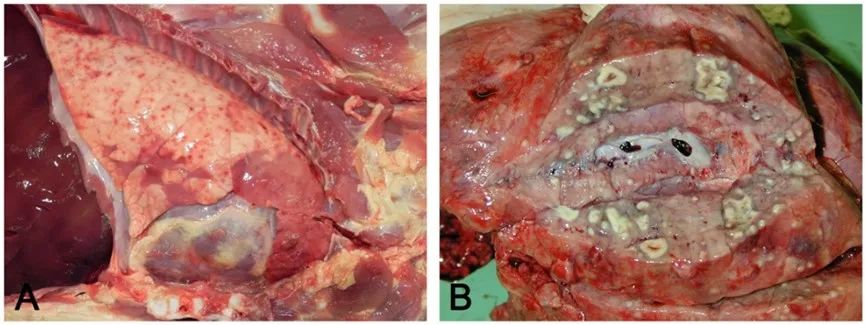

栓塞性肺炎特征是存在隨機散布的充血/出血病灶(初期)或膿腫(慢性的)。

(A)急性充血/出血病灶,通常與腸道的菌血癥有關(guān)。(B)化膿灶被正常肺實(shí)質(zhì)包圍,由于肺外化膿性靜脈炎引起的微血栓所致。